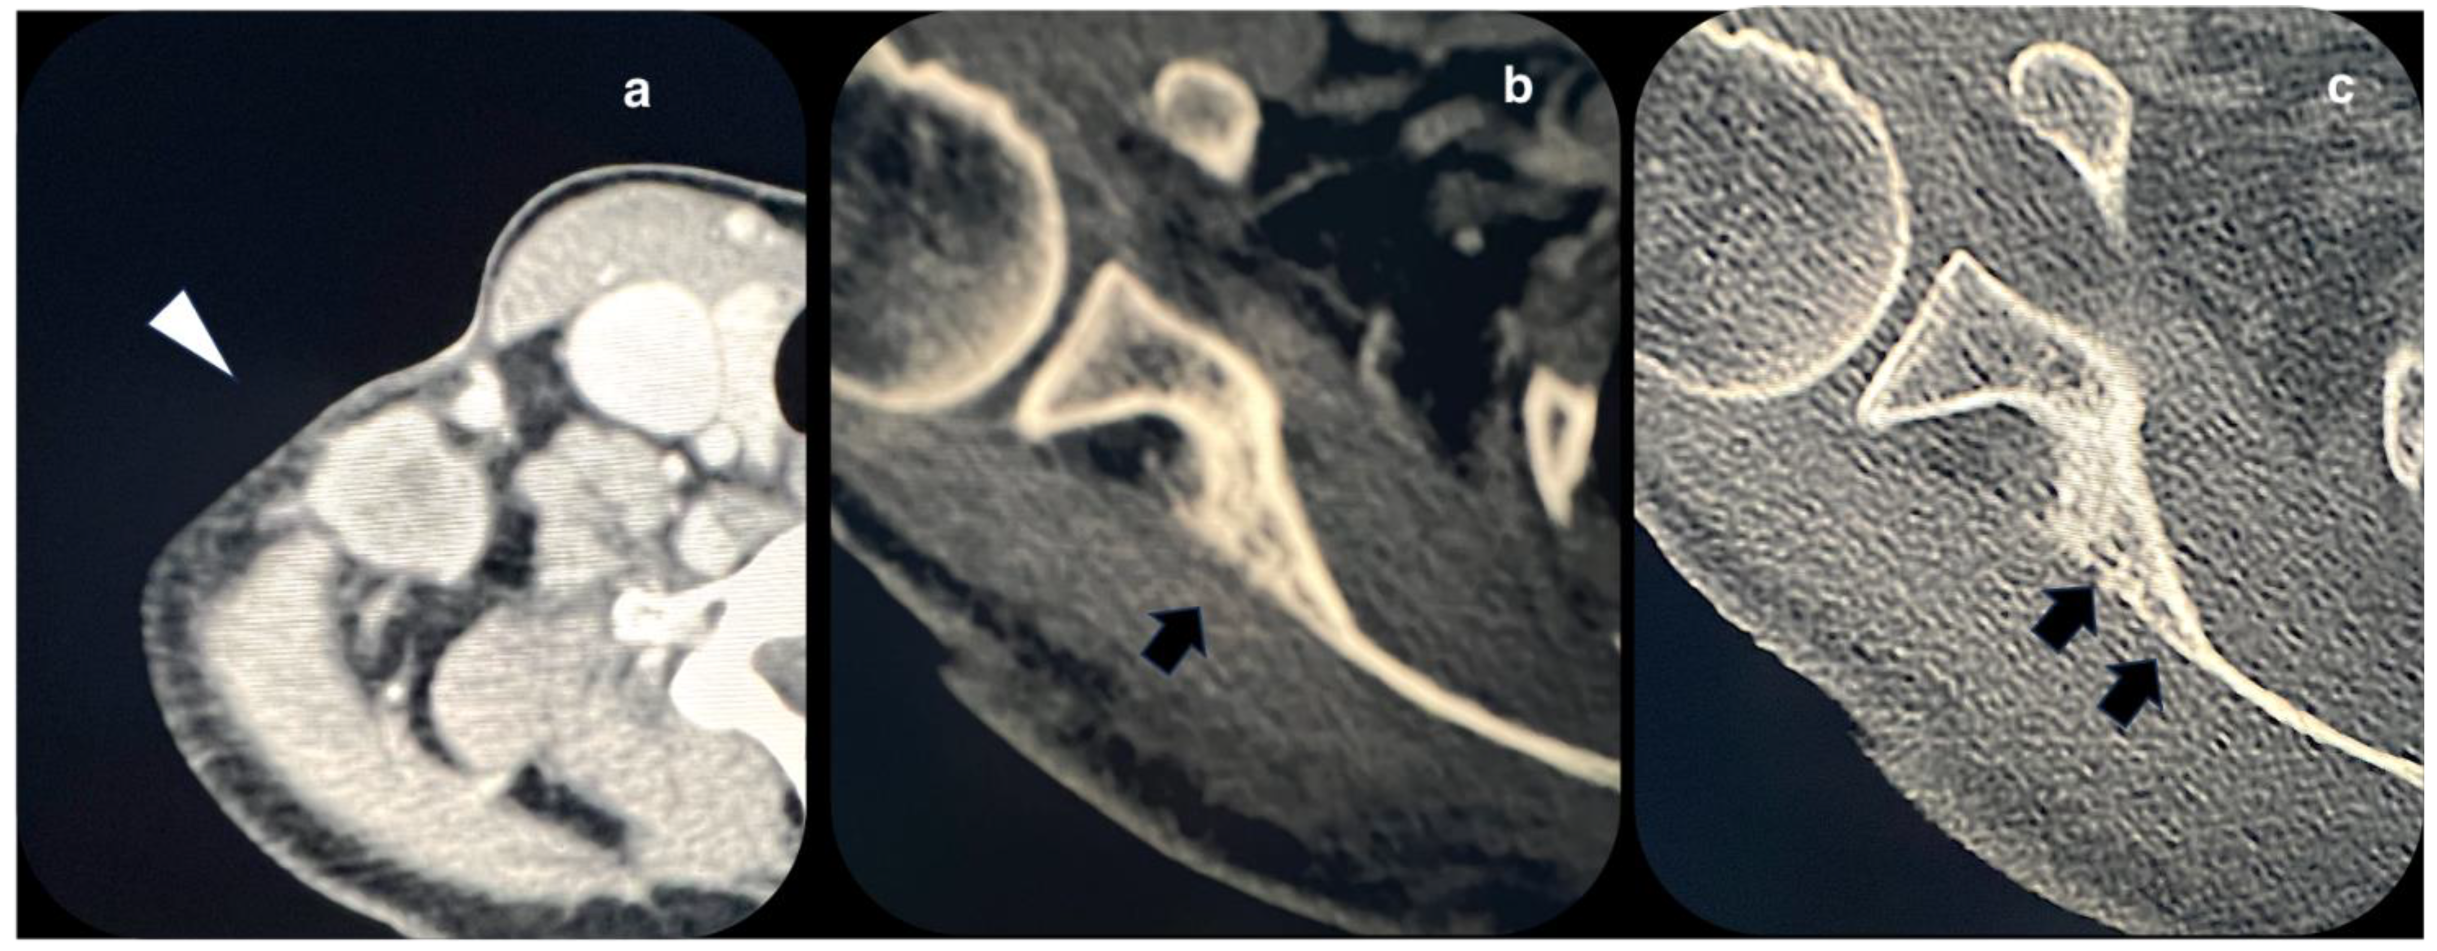

2. Case Presentation